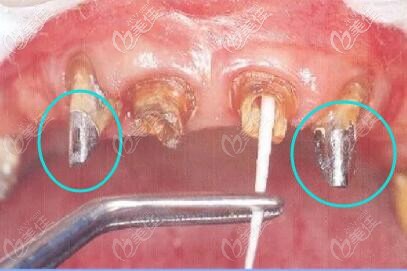

牙齒打樁,采用纖維樁和金屬樁進(jìn)行修復(fù)有什么區(qū)別呢?小編今天開(kāi)專題為大家詳細(xì)介紹下兩者的優(yōu)缺點(diǎn),你就會(huì)明白是纖維樁好還是金屬樁好。... b8754 G0 V0